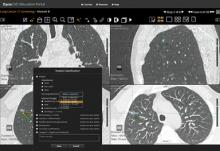

Imaging is pivotal for detection, staging and evaluation of tumor response to treatment. It is instrumental in determining which treatment is best suited to a patient and may be used to help guide surgery and radiation therapy. With chemotherapy, follow-up imaging exams are used to track tumor response and determine if different drugs should be used.